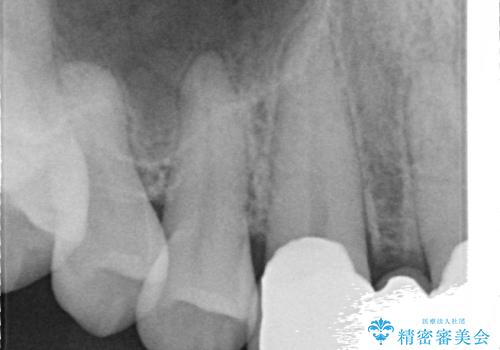

- 前歯部のすきっぱと歯並びが気になるので診て欲しいといらっしゃった方の症例です。

全顎矯正は御希望されなかったため、上顎前歯部のみの部分矯正とオールセラミッククラウンによる補綴を行いました。

今回用いたオールセラミッククラウンはジルコニアフレームという白い素材の上にセラミックを盛っているため、審美性が非常に高いのが特徴です。

また、ジルコニアは人工ダイヤモンドの材料にも使われているほど高い強度を持っており、そのためオールセラミッククラウンは審美性だけでなく、奥歯やブリッジの補綴も可能とするクラウンです。